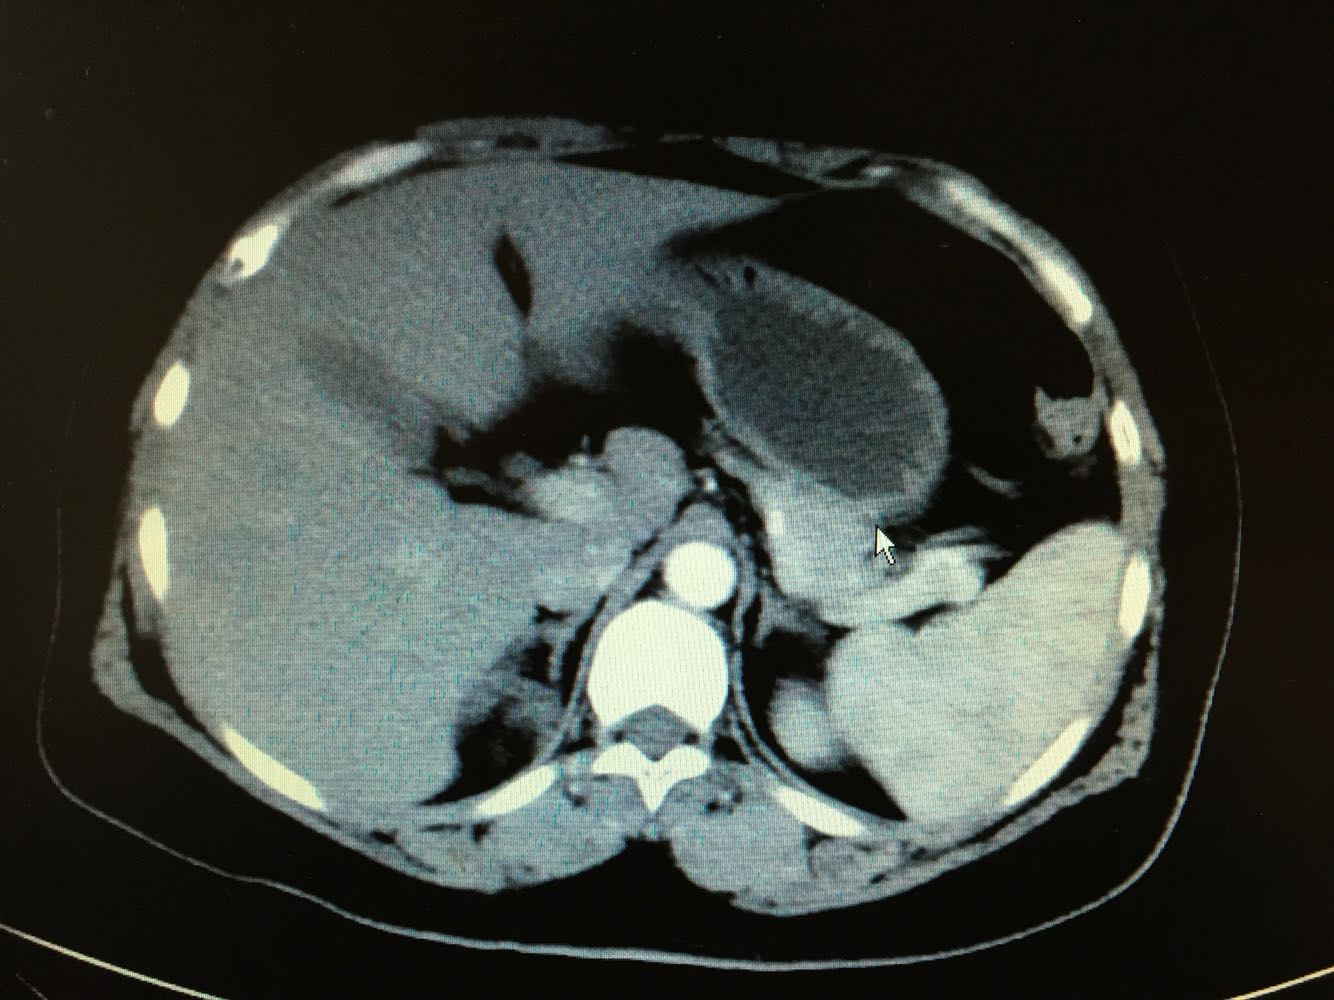

右侧肾上腺髓样脂肪瘤

体检发现右侧肾上腺占位

CT提示右侧肾上腺占位

行腹腔镜下右侧肾上腺占位切除术。 一般为无功能肾上腺腺瘤。